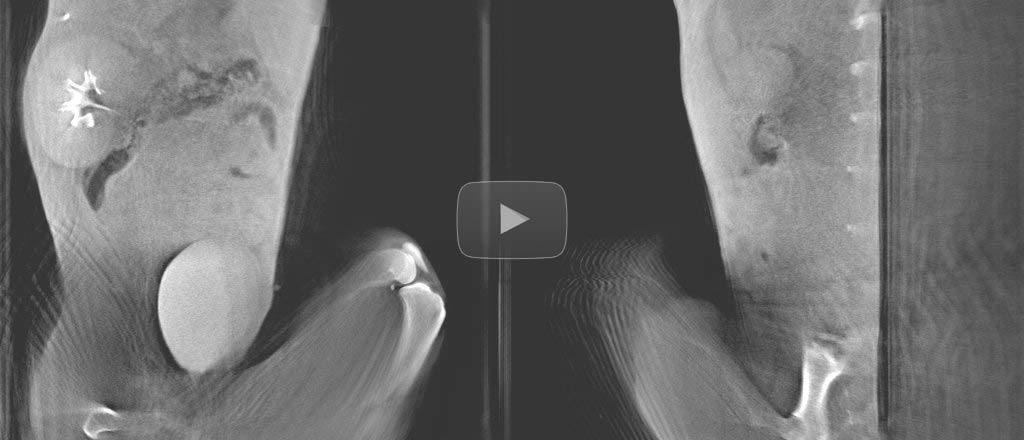

No need of a deep anesthesia and external lung ventilation setup

Breathing cycle detection on abdominal scans